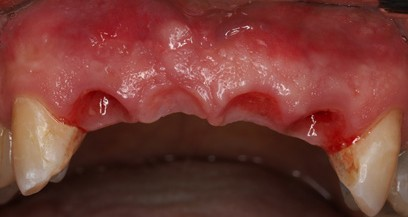

Not all clinical situations present us with ideal immediacy outcomes and staging may be the only option. The following case presented with initial plan extract teeth and immediately place implants with immediate fixed temporary. Due to lower stability at implant #7, we decided to avoid temporalization until at least 2 mo post implant placement.

Immediate implants were placed and patient was given an Essix retainer to wear for at least 6 weeks post implant placement.